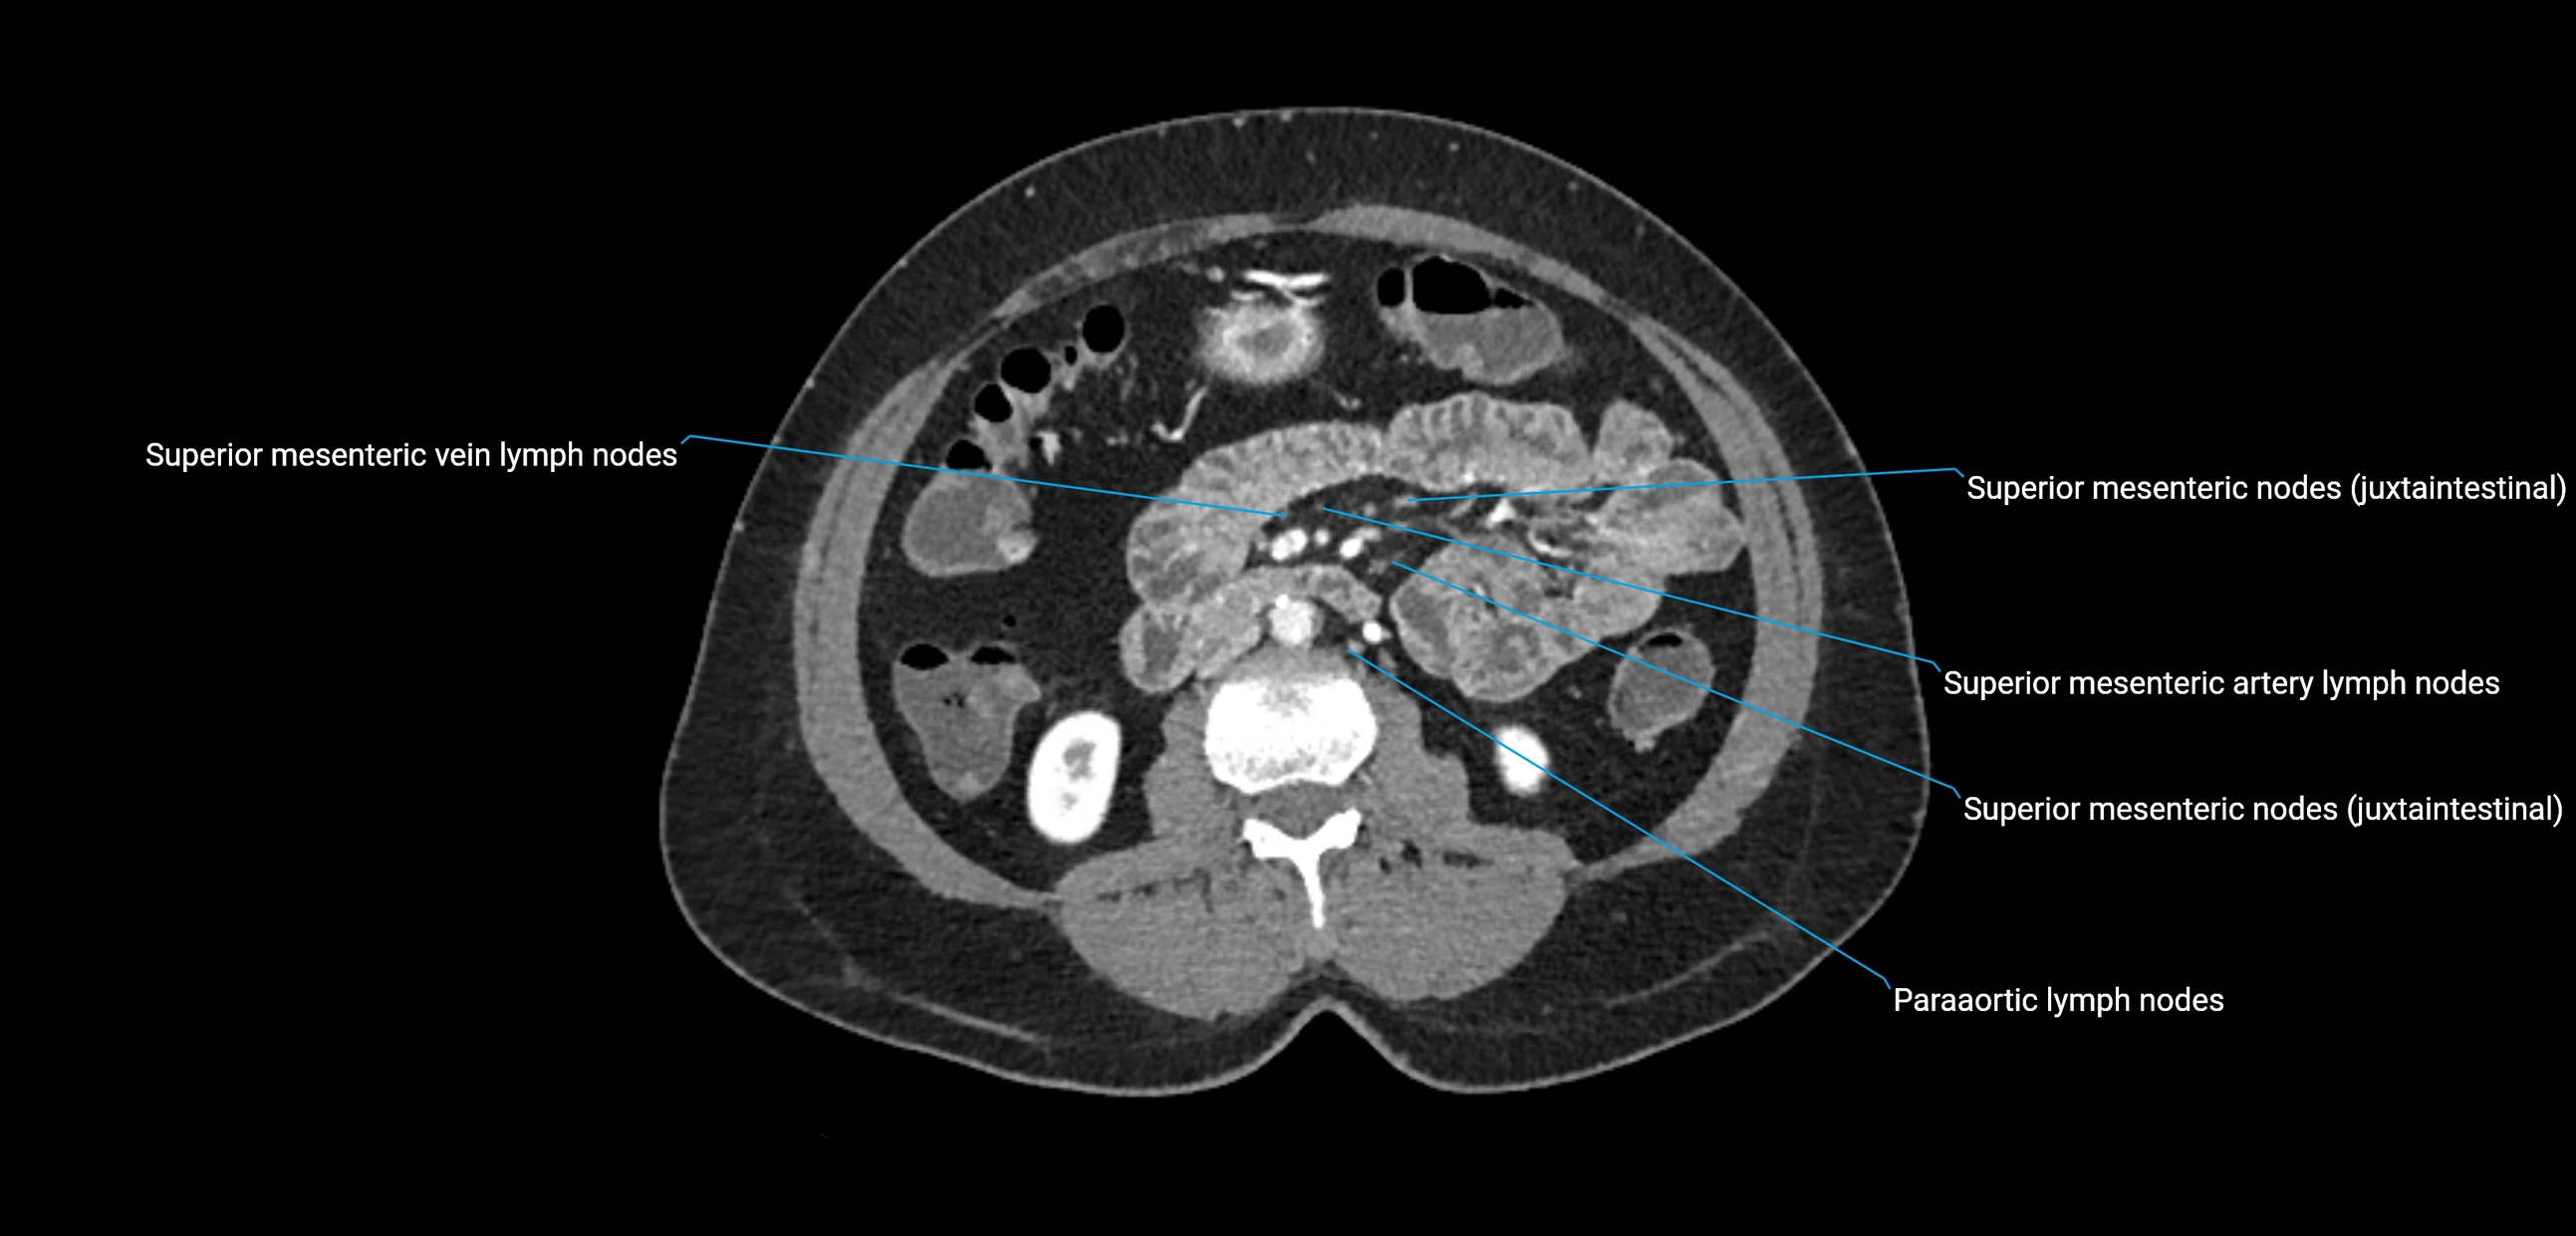

CT image

image